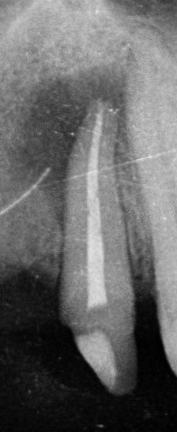

A fenti röntgenképeken egy korábban elhalt, “gócos” fog gyökérkezelés utáni gyógyulásának pillanatképei láthatóak. 1. gyökértömés pillanata 2. négy hónappal később 3. tíz hónnapal a gyökétömés után. Jól kivehető, hogy a gyökércsúcs körüli “fekete folt” fokozatosan “kifehéredik”, azaz a gyulladástól elpusztult csont visszaépül.

Amennyiben a gyökércsatornában lévő baktériumok eltávolításra kerülnek és a csatornarendszert hermetikusan zárjuk, jó esély kínálkozik a szervezet számára, hogy a bacik okozta észrevétlen gyulladás mérete fokozatosan csökkenjen majd megszűnjön. A létrejött csontdefektust 1-2-3 év alatt reparálódik, az elpusztult csont visszaépül.